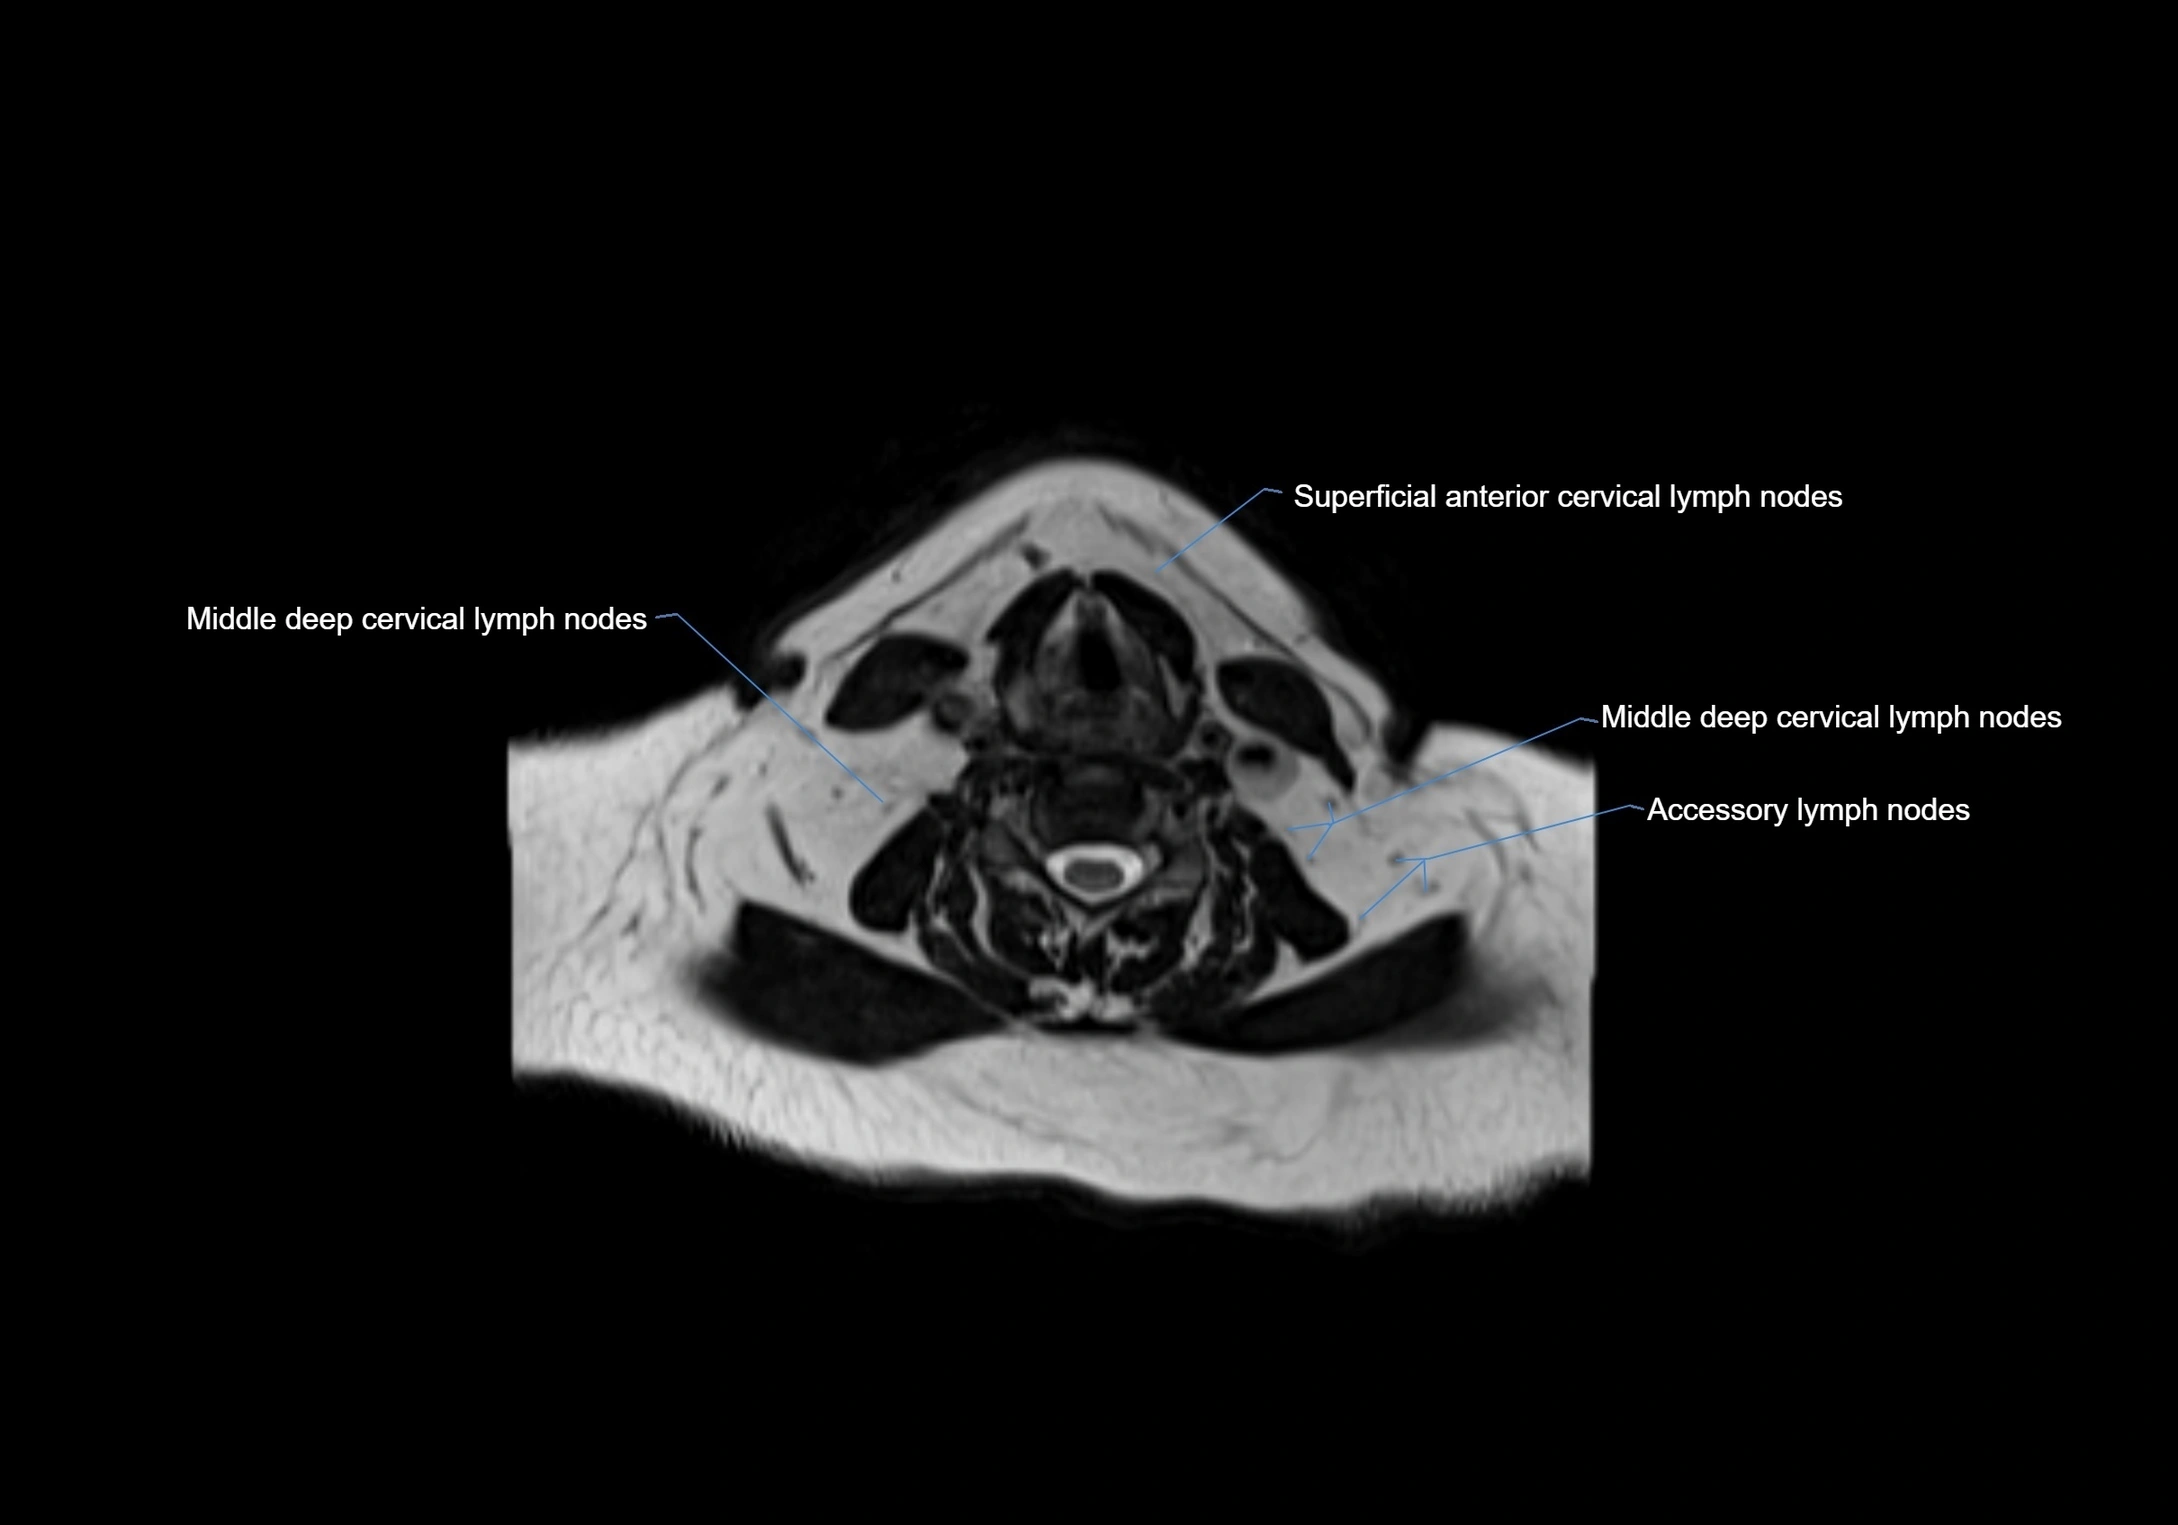

Accessory lymph nodes

Accessory lymph nodes are small, secondary lymph nodes located along the main facial and cervical lymphatic chains, often adjacent to primary lymph nodes, such as preauricular, submandibular, or occipital nodes. They are typically less than 5 mm in diameter, embedded within subcutaneous fat or connective tissue, and may be variable in number and location. These nodes provide additional filtration and immune surveillance for lymph collected from the face, scalp, and neck regions. Accessory lymph nodes are usually non-palpable in healthy individuals but may enlarge in response to infection, inflammation, or metastasis, making them clinically significant.

Location

• Found along primary lymph node chains, including preauricular, submandibular, parotid, and occipital regions

• Embedded in subcutaneous fat or superficial fascia, often lateral or posterior to primary nodes

• Variable in number; may occur unilaterally or bilaterally, depending on individual anatomy

MRI Appearance

T2-weighted images:

• Nodes show intermediate signal, with surrounding fat bright

• Useful for detecting edema, inflammation, or infiltration

• Fatty hilum may appear slightly hyperintense relative to cortex

MRI images

image